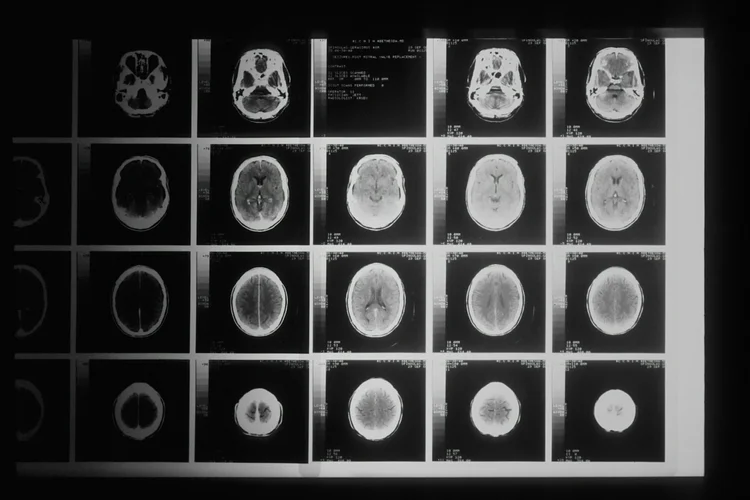

We use some cutting age artificial intelligence (AI) in our clinical practice.

I recently had the opportunity to speak with Medscape about the intersection of AI and medical education. One message stands out: good data in, good data out - a classic concept from data science and analytics that is crucial to understand for all that use AI in medicine.

As AI becomes more integrated into healthcare decision-making (soon to be the norm for much of the workforce), all clinicians must consider these important questions:

These questions remind us that AI is only as good as the data it is trained on. For AI to be truly effective and safe in healthcare, clinicians need to be equipped not just with the ability to trust AI outputs, but with the tools to critically assess them.